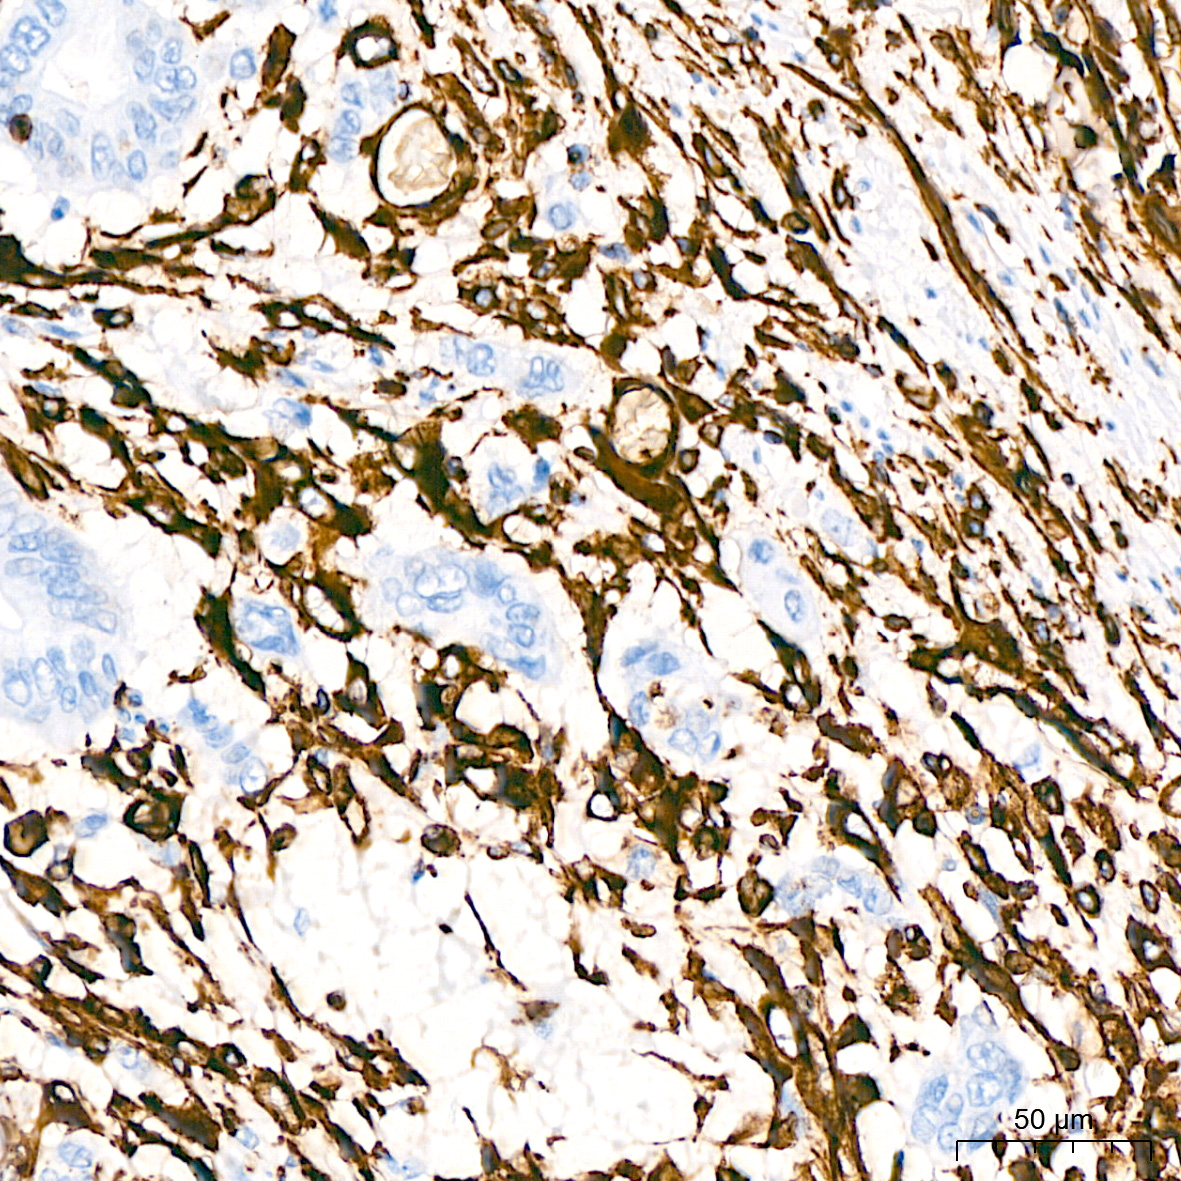

细胞外基质(Extracellular matrix, ECM)是细胞外分泌的大分子的复杂网络,其主要功能涉及细胞和组织的结构支架和生化支持。ECM可分为基底膜(BM)和间质基质(IM)。基底膜(BM)由胶原、层黏连蛋白、PGs和FN组成,位于薄壁组织和结缔组织之间的界面,可作为癌细胞侵袭、浸润和外渗的结构屏障。IM是一种松散的ECM,由胶原蛋白I和III、弹性蛋白纤维和糖蛋白组成,在肿瘤进程中,IM中的胶原纤维更厚、更致密。赖氨酰氧化酶(LOX)家族催化胶原交联的形成,在肿瘤中,LOX表达增加导致胶原过度交联,硬度增加,从而引起肿瘤中的固体应力。除胶原改变外,ECM中还有各种糖蛋白的病理表达,所有这些都形成一个生态位,促进细胞迁移、黏附和转移。